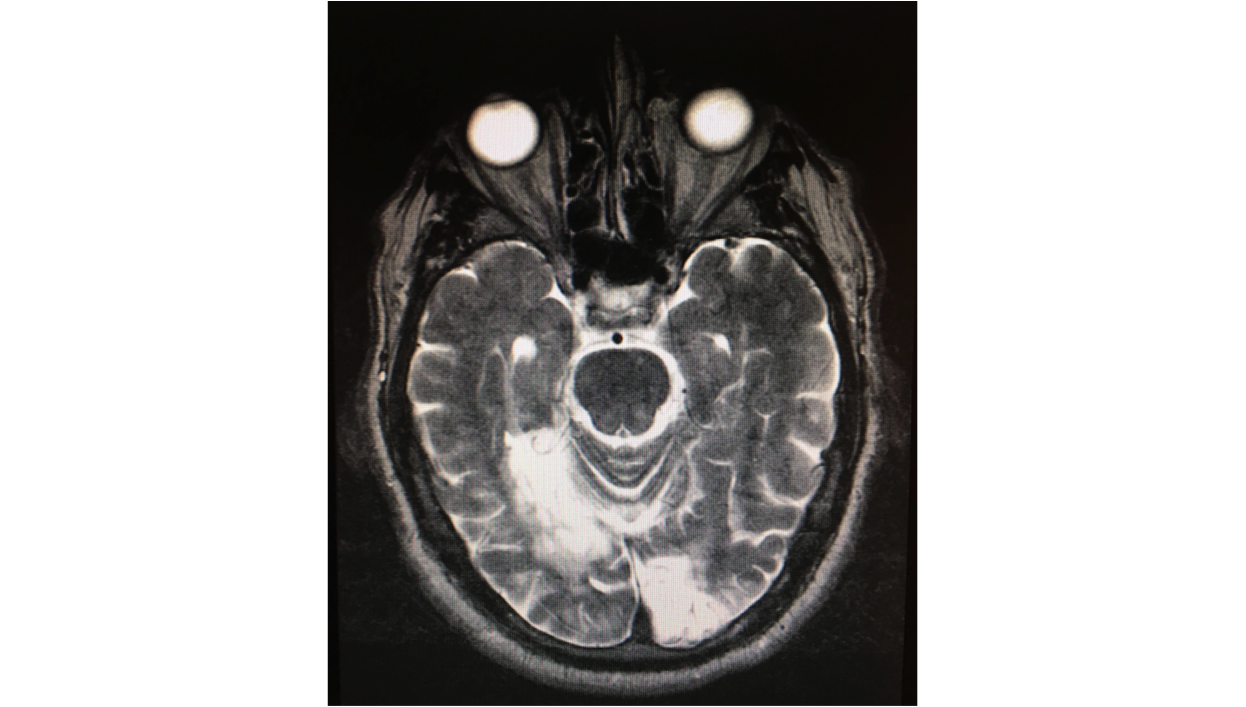

Diagnostic procedures

- Humphrey Visual Field (the automated visual field is rarely completely symmetric)

- Goldmann Visual Field

- CT scan

- Magnetic resonance imaging

This disease process can be due to trauma, bilateral multiple sclerosis lesions, cerebral infarcts or viper bite. Most of the cerebral infarcts are derived principally by embolization of the calcarine arteries from basilar or vertebral branches. There has been one documented case of CQHH from the University of Rome, Institute of Ophthalmology from 1995 in a patient with multiple sclerosis[2].

The most frequent cause is embolization of the calcarine arteries (from basilar or vertebral branches) or from thromboembolism from cardiac disease [9].

Most of the cases are related to ischemic or hemorrhagic stroke, associated to spontaneous thromboembolism, cervical-vertebral trauma, vessel dissection and one case of viper bite.